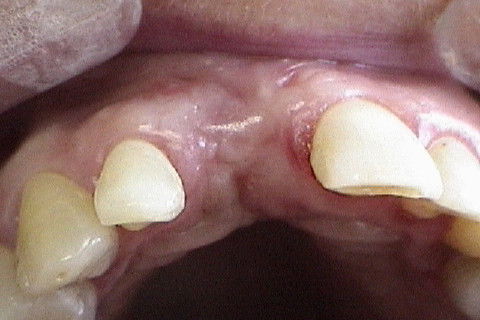

Vista oclusal no momento da reabertura cirúrgica(6 meses após)

Vista vestibular da colocação do cicatrizador com perfil de emergencia